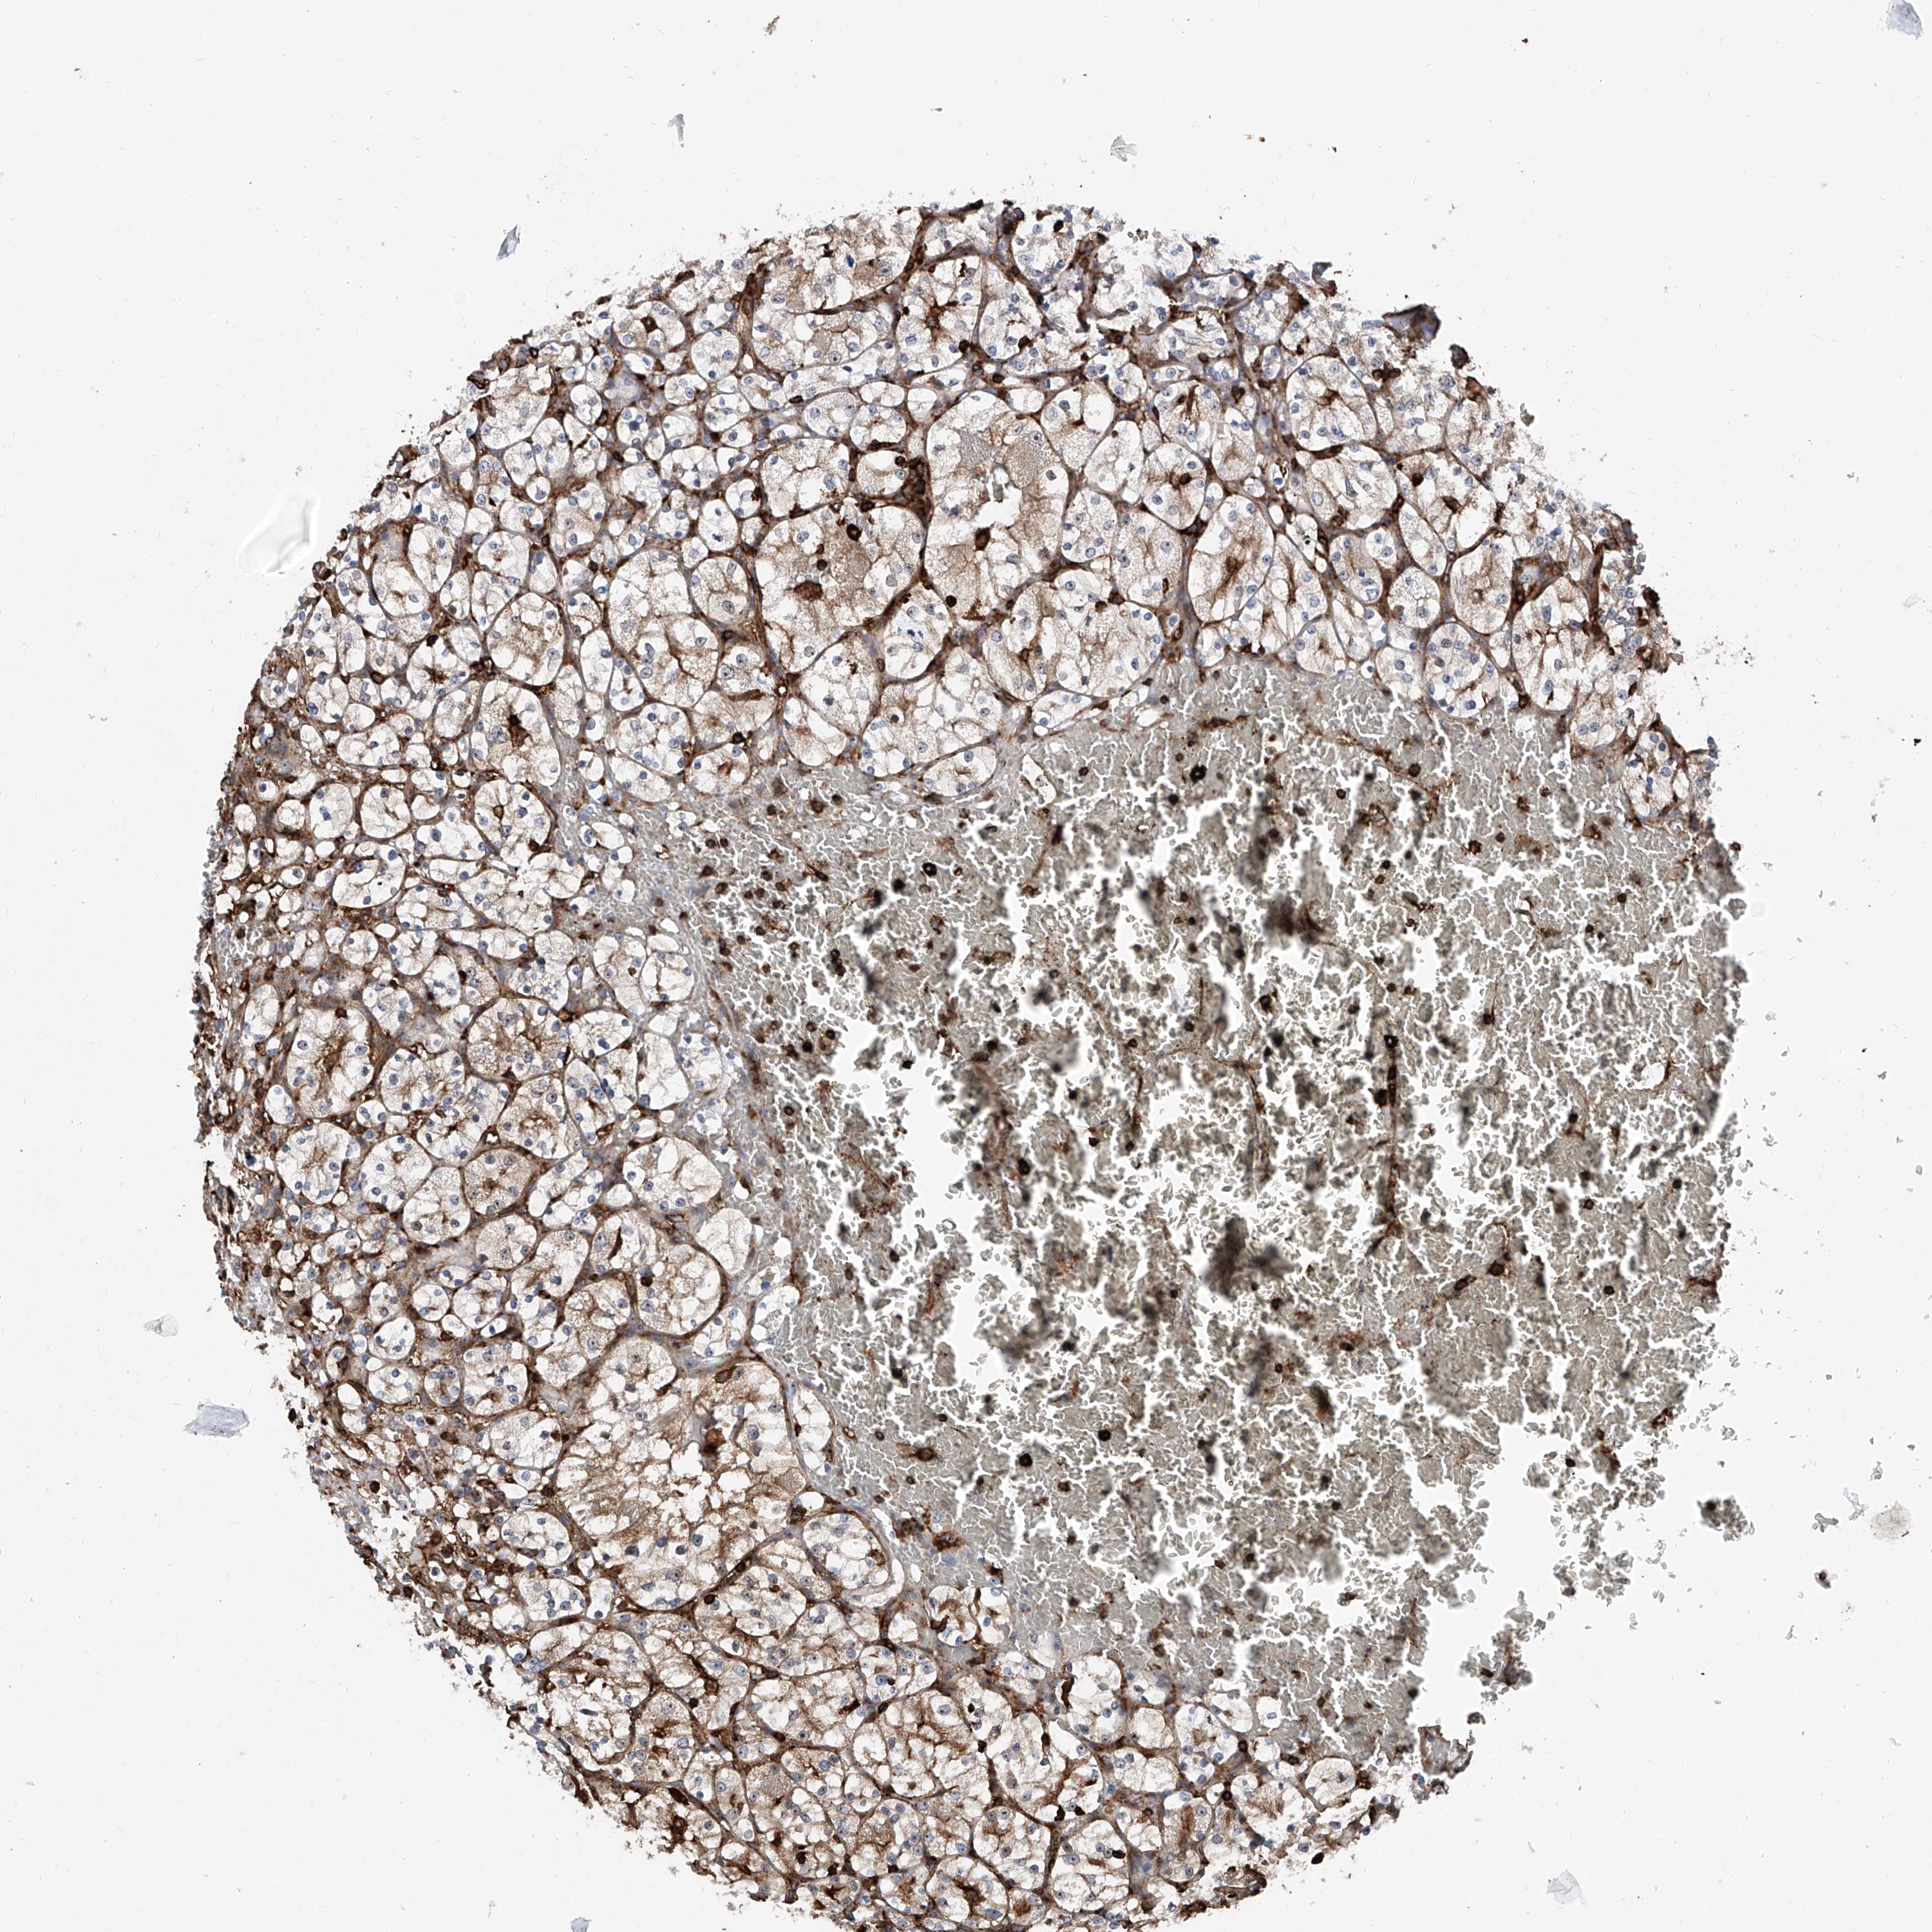

KIDNEY RENAL CLEAR CELL CARCINOMA (VALIDATION) - Interactive survival scatter ploti

The Survival Scatter plot shows the clinical status (i.e. dead or alive) for all individuals in the patient cohort, based on the same data that underlies the corresponding Kaplan-Meier plots. Patients that are alive at last time for follow-up are shown in blue and patients who have died during the study are shown in red.

The x-axis shows the expression levels (FPKM) of the investigated gene in the tumor tissue at the time of diagnosis. The y-axis shows the follow-up time after diagnosis (years). Both axes are complimented with kernel density curves demonstrating the data density over the axes. The top density plot shows the expression levels (FPKM) distribution among dead (red) and alive patients (blue). The right density plot shows the data density of the survived years of dead patients with high and low expression levels respectively, stratified using the cutoff indicated by the vertical dashed line through the Survival Scatter plot. This cutoff is automatically defined based on the FPKM cutoff that minimizes the p-score. The cutoff can be changed by dragging the vertical line or by entering a cutoff value in the square labeled "Current cut-off".

Under the Survival Scatter plot the p-score landscape (black curve; left axis) is shown together with dead median separation (red curve; right axis). Dead median separation is the difference in median mRNA expression between patients who have died with high and low expression, respectively. It is calculated as follows: median FPKM expression of dead patients with high expression - median FPKM expression of dead patients with low expression. This is intended to aid the user in visually exploring custom cutoffs and the associated p-scores and dead median separation.

Individual patient data is displayed and can be filtered by clicking on one or more of the category buttons on the top of the page. Categories describing expression level and patient information include: high, low, alive, dead, female, male and tumor stages. The scale of the x-axis can be toggled between linear and log-scale by clicking on the "x log" button. Mouse-over function shows TCGA ID, patient information and mRNA expression (FPKM) for each patient.

& Survival analysisi

Kaplan-Meier plots summarize results from analysis of correlation between mRNA expression level and patient survival. Patients were divided based on level of expression into one of the two groups "low" (under cut off) or "high" (over cut off). X-axis shows time for survival (years) and y-axis shows the probability of survival, where 1.0 corresponds to 100 percent.

ZNF484 is validated prognostic, high expression is favorable in Kidney Renal Clear Cell Carcinoma (validation)

: 3.72

Average pTPM 3.5

Number of samples 100